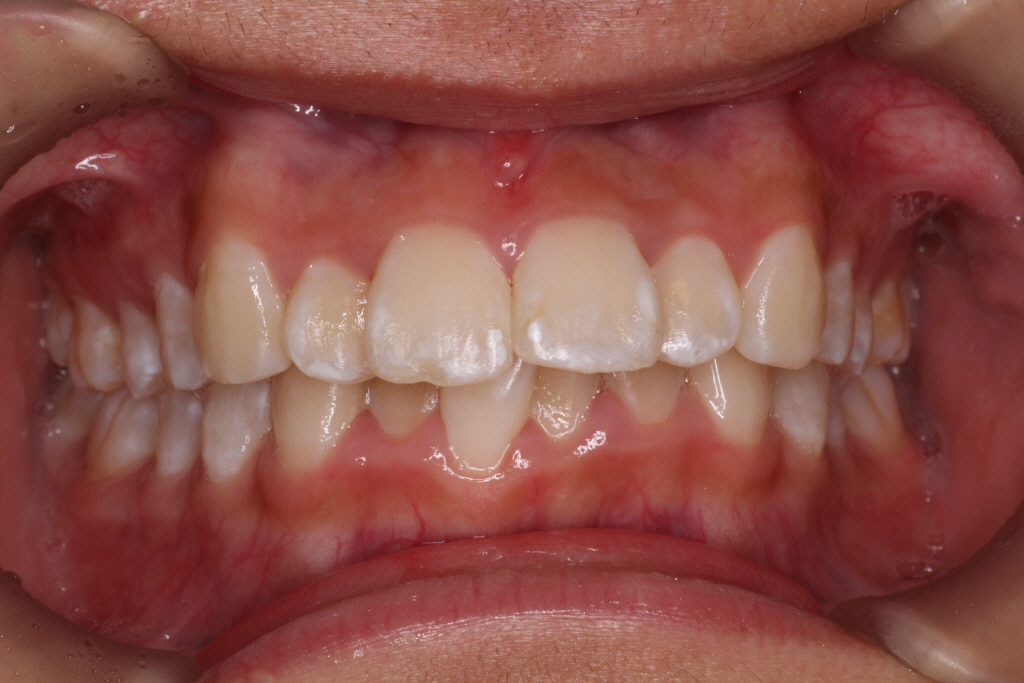

最後のアライナーが終わった時の口腔内写真です。

前歯のがたつきはなくなり、カリエール後にできていた隙間もなくなっています。

奥歯も1歯対2歯の関係で咬めていることがわかります。

通常は歯の並びを微調整するために口腔内を再スキャンし、歯の並びを再設計すること(リファイメント) を2,3回行いますが今回のケースは一回目で満足のいく結果が得られたのでここで保定期間に入りました。